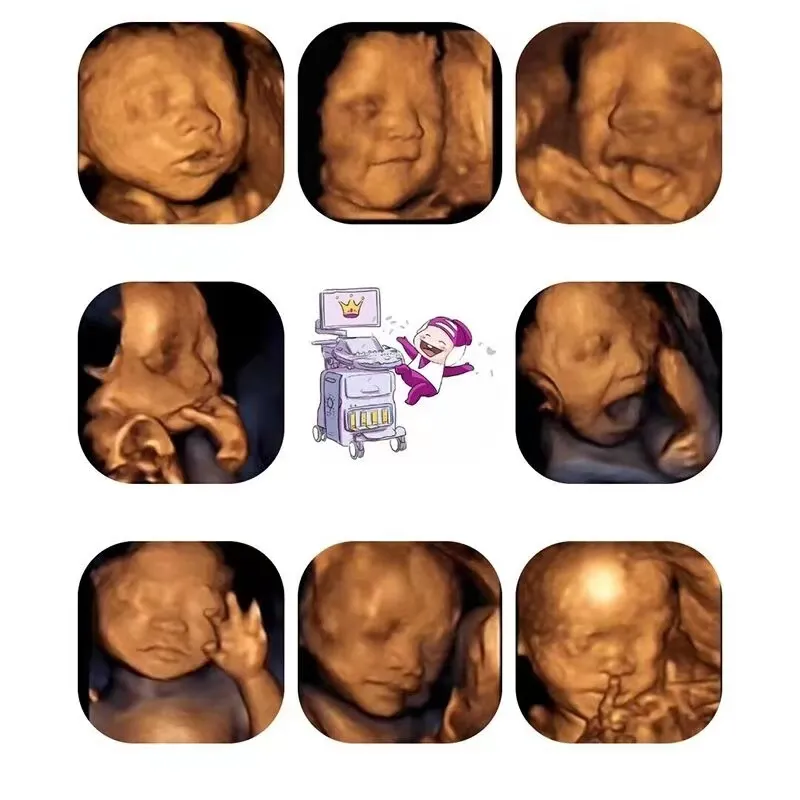

四维彩超,作为必不可少的孕检项目之一,也是孕期能提前看到宝宝模样的项目。所以,四维彩超对准爸妈来说有着非常特殊的含义,不过总有孕妈粉丝给小百留言:自己看完宝宝的四维彩超图相当的失望。

因为实在是——太!丑!啦!

还好宝宝出生后比四维照片好看很多,白白胖胖的,这才让孕妈妈放心。仔细瞅瞅,孩子的一些动作和表情,又跟四维照片和视频里胎儿几乎一模一样,就感觉非常神奇。

四维彩超的检查有一定的时间限制,检查的建议时间单胎为孕20-24周(+6天),双胎为孕20-22周,不同时期的胎宝宝各部位发育程度和相貌都是不一样的。

另外,孕25周左右的胎儿身上有厚厚的胎脂,这些胎脂能够保护胎儿,但是胎脂让胎儿看起来脏兮兮的,拍出来的照片也会坑坑洼洼的感觉很不好看。

为了能够更好的筛查这些畸形,在检查的时候,医生会通过各个不同的角度,找合适的位置来检查,而且还会把某些位置放大检查。

这就意味着,无法选择较佳的角度给胎儿拍照,所以会把本来还是比较可爱的胎儿,拍的鼻子扁嘴巴大,有些难看。

胎儿是生活在羊水中的,这些羊水不仅能够为胎儿提供营养,让胎儿感觉温暖,还能起到缓冲的作用。但是在拍照的时候,这些羊水会变成一种阻碍,它们影响了拍照的效果,让胎儿看起来很难看。